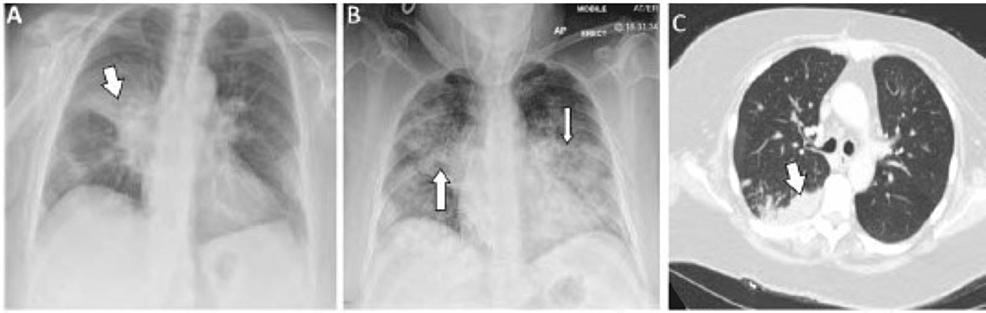

Adenocarcinoma is a tragically common iteration of lung cancer. Risk factors included primary or secondary exposure to tobacco smoke, family history of the disease, and occupationally related hazards, among others. Metastasis to various distant organs may pre…